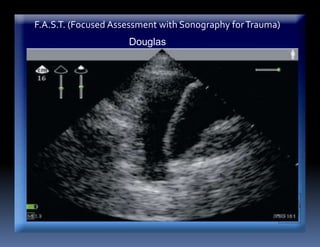

F.A.S.T. (Focused Assessment with Sonography forTrauma)

Douglas

ESTUDIOS COMPLEMENTARIOS

ECOTRAUMA

y una especificidad del 100%

Ej: Líquido en FS Douglas- Hemoperitoneo